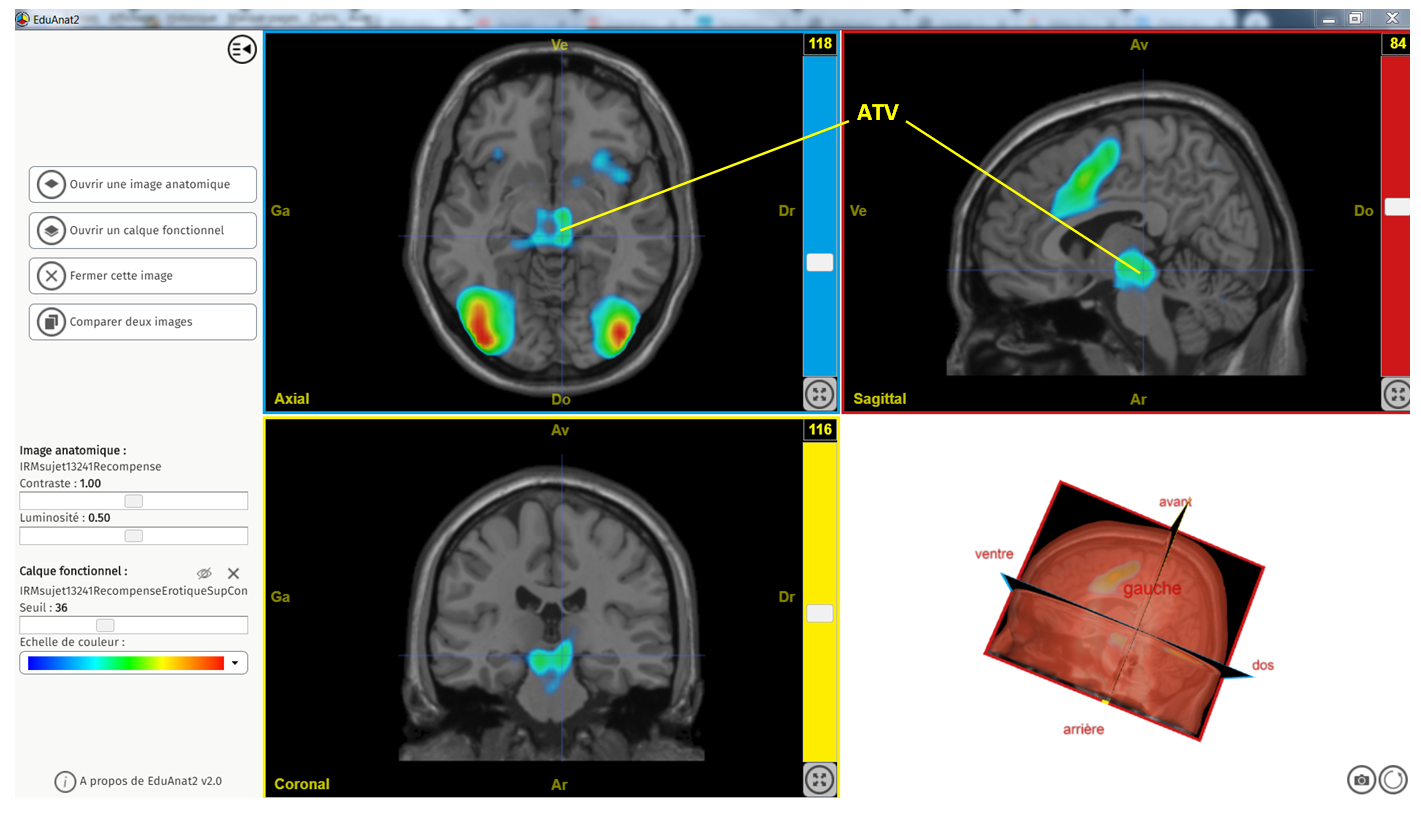

ATV legendée erotique sup controle